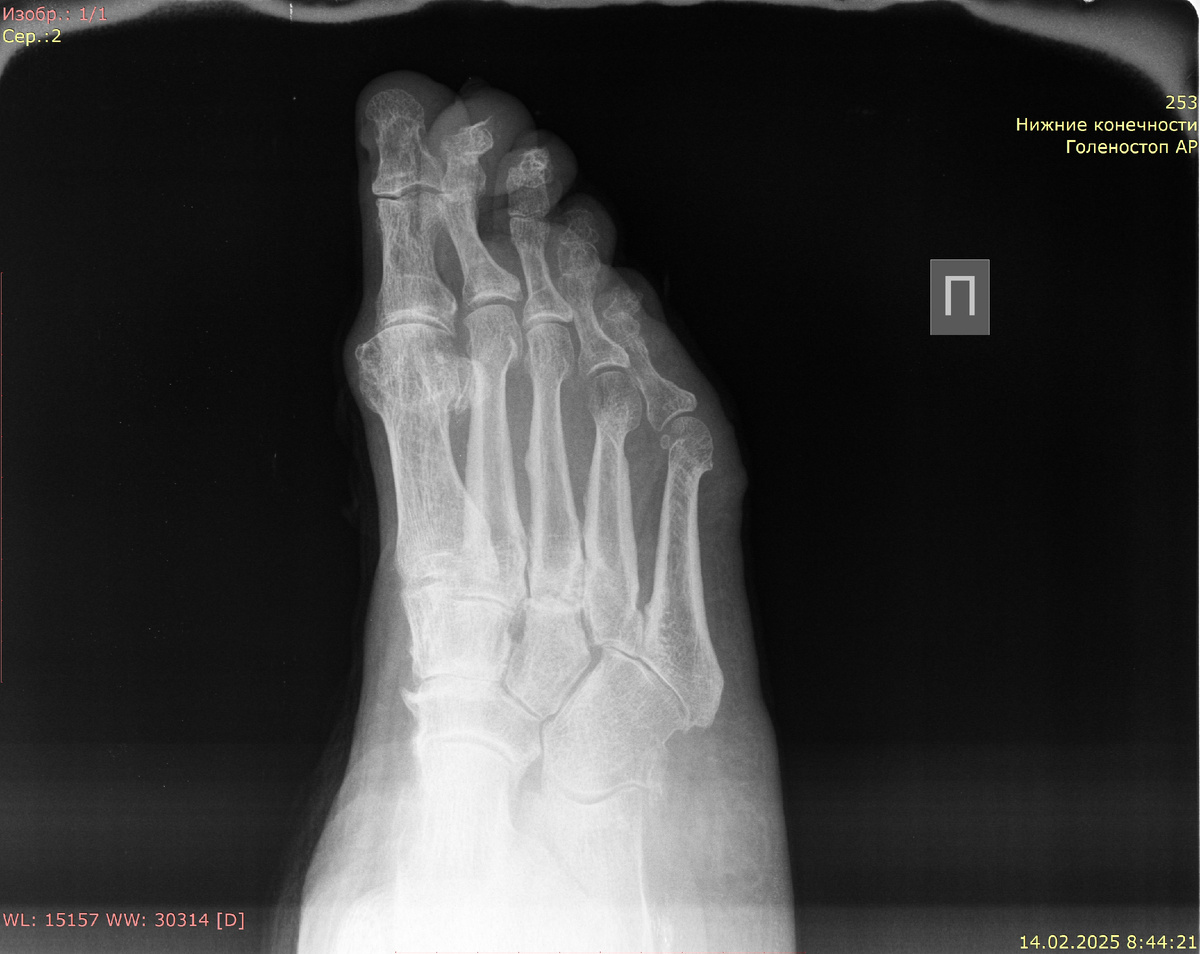

Рентгенография правой стопы в прямой и косой проекциях:

Аномалий развития не выявлено. Форма, размеры и структура костей стопы не изменены. Просветы суставных щелей в суставах стопы неравномерно сужены. Суставные поверхности уплотнены, в субхондральном слое остеосклероз. Оссификаты по краю суставных поверхностей. Костно-травматических и костно-деструктивных изменений не выявлено. Мягкие ткани без патологических рентгенопозитивных включений.

Заключение: артроз суставов правой стопы II-III степени по Келлгрену-Лоуренсу. Костно-травматических изменений не выявлено